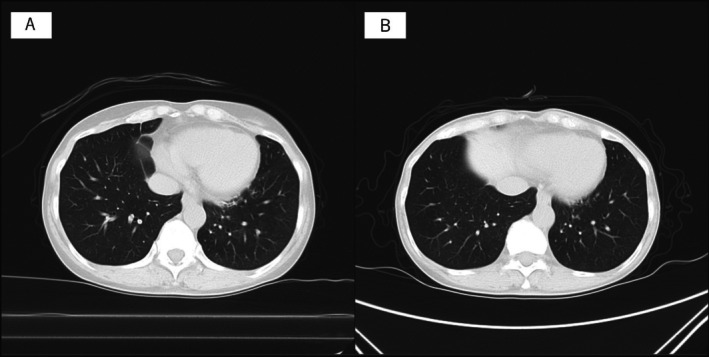

2019冠状病毒病(COVID-19)可导致呼吸系统后遗症,包括支气管扩张。虽然结核病后的支气管扩张是许多细菌感染/定植的滋生地,但很少有报道称COVID-19后的支气管扩张是细菌感染/定植的温床。我们报告了一例69岁的女性,她在COVID-19肺炎后出现支气管扩张。患者在新冠肺炎前5年胸部CT未见异常。她在COVID-19后出现持续咳嗽和痰,在COVID-19后的胸部CT显示新的支气管扩张。一年后,因慢性呼吸道感染反复加重,痰中检出流感嗜血杆菌,转至我科就诊。该病例突出了流感嗜血杆菌在covid -19后支气管扩张中感染/定植的可能性。虽然到目前为止,COVID-19后慢性气道感染合并支气管扩张的报道很少,但长期呼吸随访和细菌定植管理对这些患者未来至关重要。该病例提示,在支气管扩张的情况下,COVID-19可使个体易发生细菌感染,这强调了在COVID-19后气道管理中保持警惕的必要性。

Coronavirus Disease 2019 (COVID-19) can lead to respiratory sequelae, including bronchiectasis. While bronchiectasis following tuberculosis is a breeding ground for many bacterial infections/colonisation, there are few reports of bronchiectasis following COVID-19 being a hotbed for bacterial infection/colonisation. We present a case of a 69-year-old female who developed bronchiectasis following COVID-19 pneumonia. The patient had no abnormal findings on chest CT scan for 5 years before COVID-19. She developed persistent cough and sputum after COVID-19 and chest CT just after COVID-19 revealed new bronchiectasis. One year later, she was introduced to our department for repeating exacerbation of chronic respiratory infection, and Haemophilus influenzae was detected in sputum. This case highlights the potential for H. influenzae to infect/colonise in post-COVID-19 bronchiectasis. While there have been few reports of chronic airway infection complicating bronchiectasis after COVID-19 until now, long-term respiratory follow-up and management of bacterial colonisation are crucial in these patients in the future. This case suggests that COVID-19 can predispose individuals to bacterial infection in the setting of bronchiectasis, emphasising the need for vigilance in post-COVID-19 airway management.